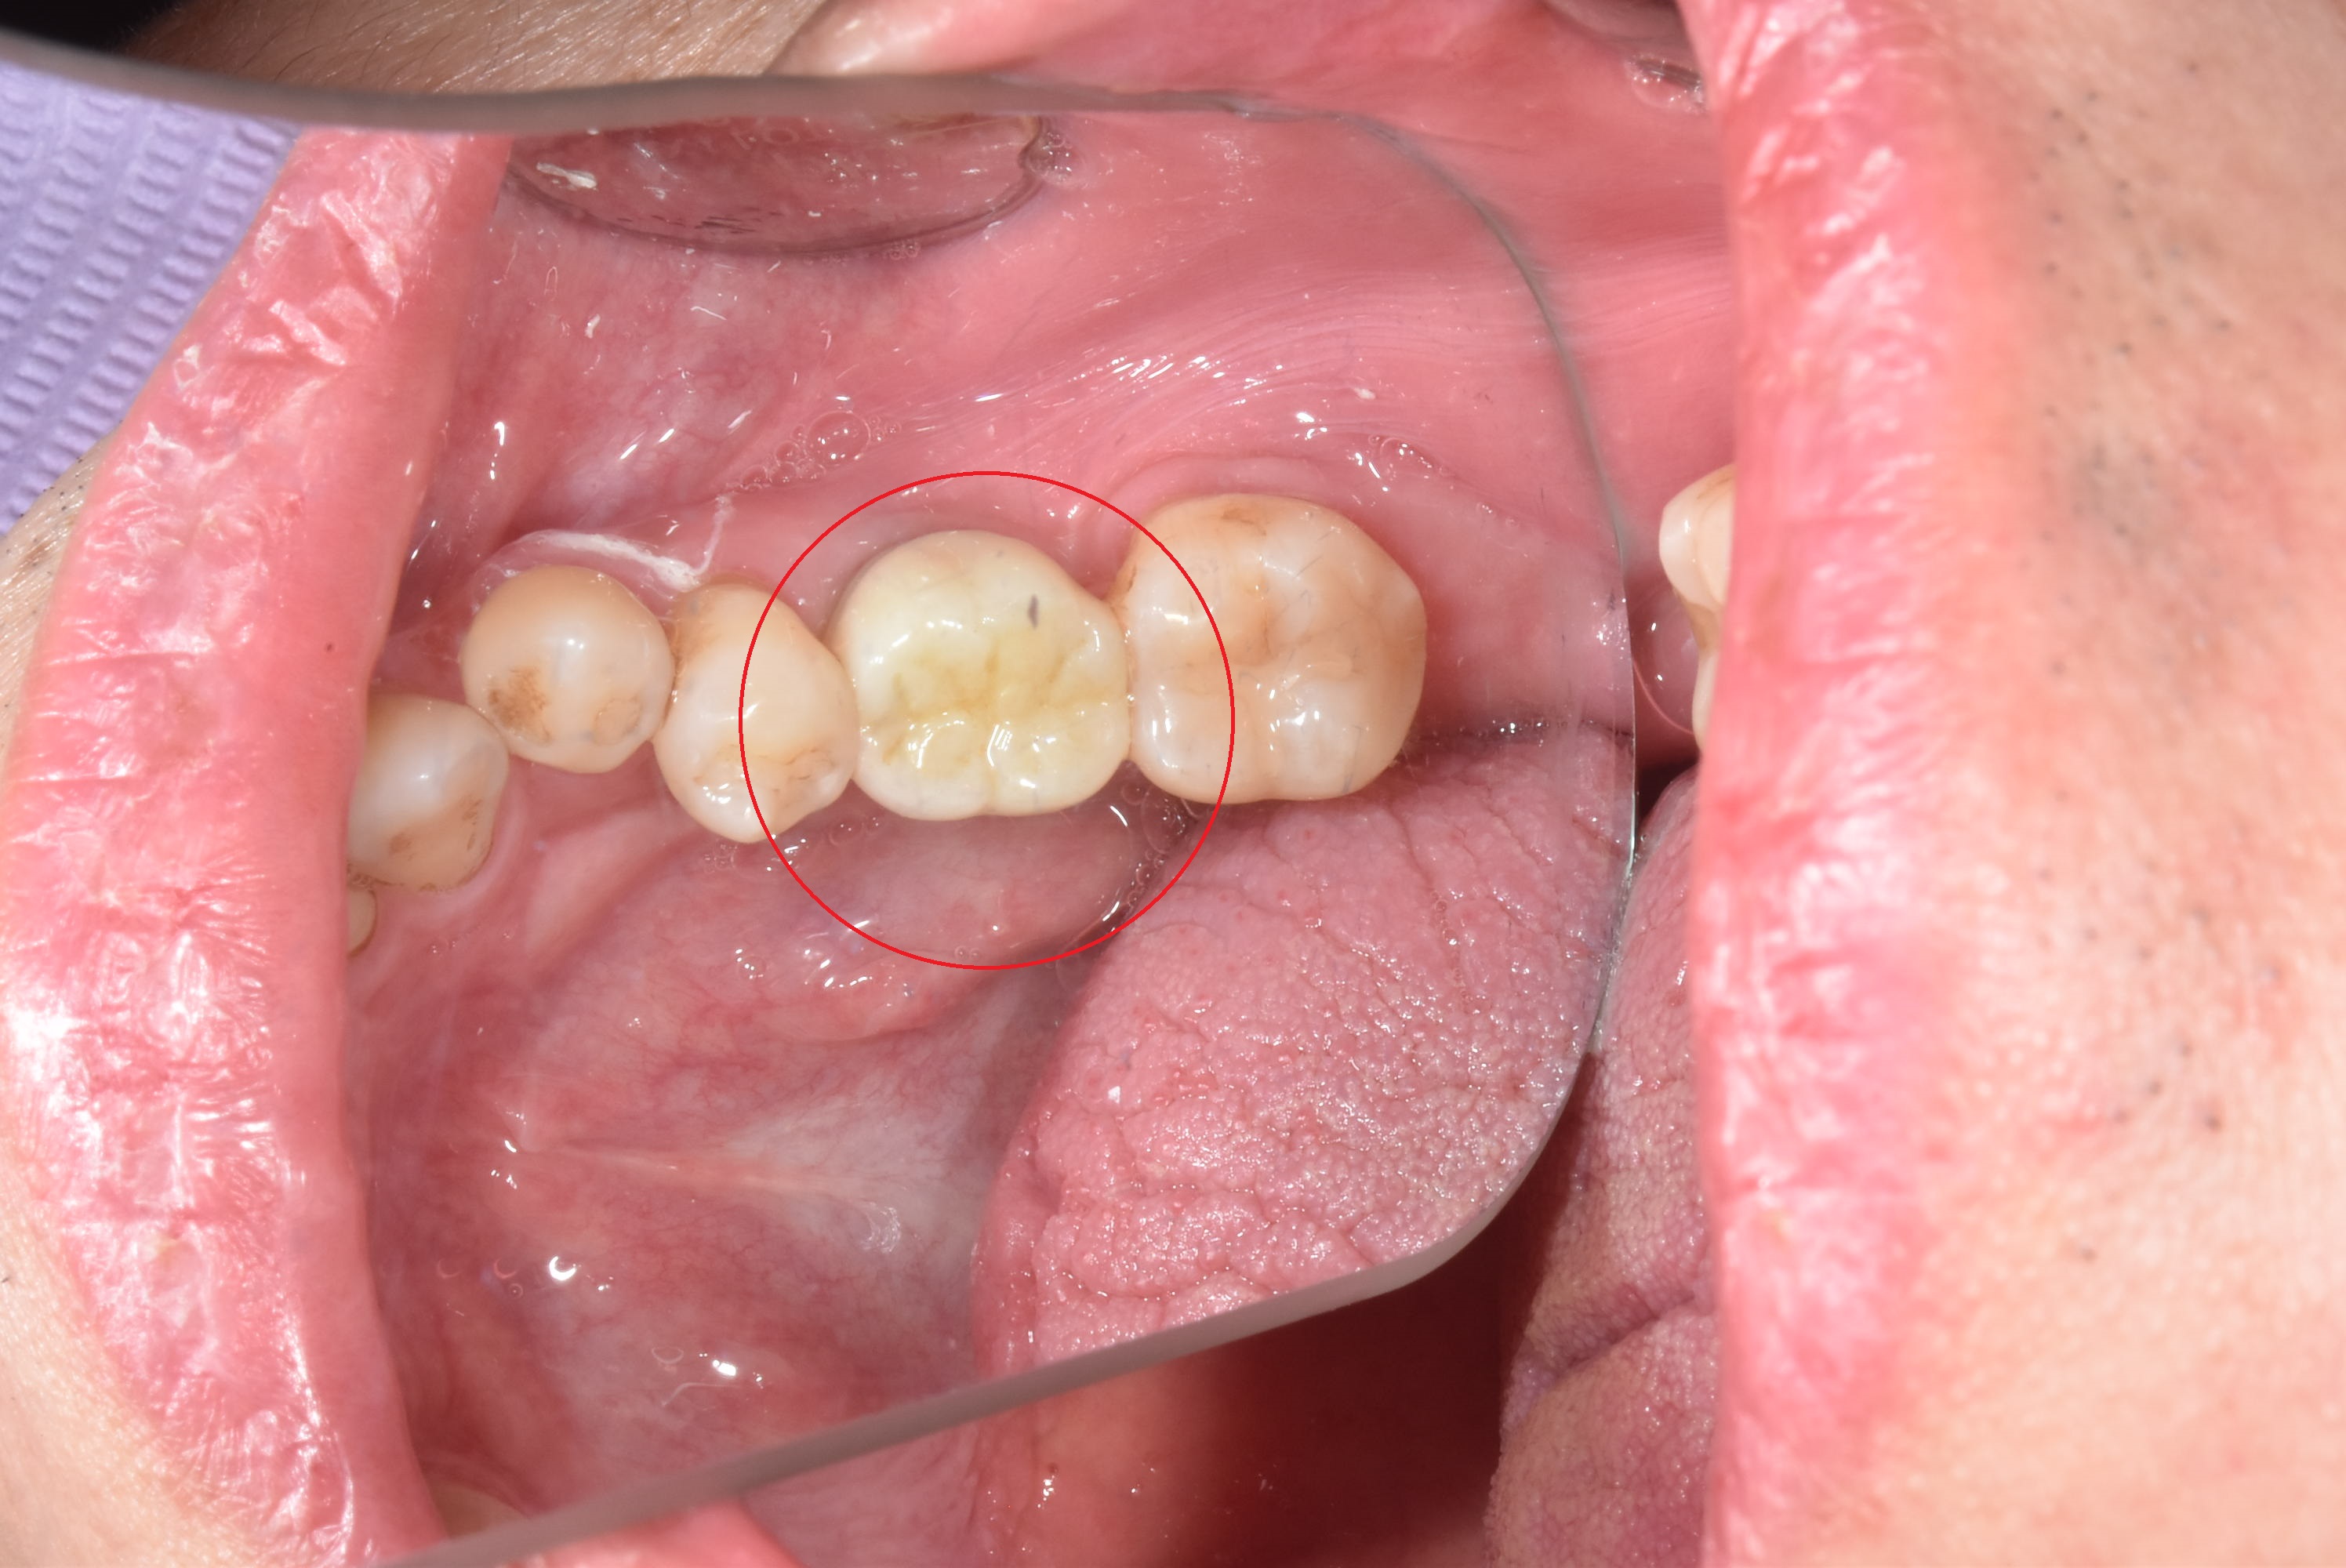

案例二

立即拔除壞牙根

當天完成植牙手術,並鎖上癒合螺帽

2-3月癒合,取下癒合螺帽,透過數位口掃至技公所製作假牙

7-10天完成假牙,試戴、調整咬合高度並鎖上,封填,完成